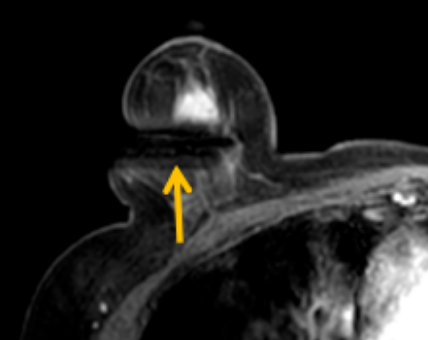

陳寶瑩評估圖像后發(fā)現(xiàn)病變?yōu)閮H僅在磁共振增強時顯示,為非腫塊樣病變,比較散,必須取得足夠多的組織才能確保病理檢查的準確性,常用的核芯針活檢獲取的組織較少,因此最終確定了磁共振引導下行真空輔助抽吸旋切活檢。取得患者及家屬認可后,陳寶瑩帶領(lǐng)團隊開始進行術(shù)前準備。

針對患者乳房小固定難度大這一問題,陳寶瑩通過巧妙體位和固定器的調(diào)整,順利固定好乳房。經(jīng)過磁共振多模態(tài)掃描,陳寶瑩找出病變活性成分相對集中區(qū)域,精準確定穿刺路徑,置入引導針、旋切針,到位后多角度旋切取出足量組織,拔除旋切針后即時行磁共振掃描,精準取得組織且術(shù)區(qū)出血很少,遂加壓包扎,整個過程非常順利,旋切活檢后患者回家休息。兩天后隨訪,李女士沒有任何不適,五天后皮膚上幾毫米的小切口已經(jīng)愈合。最終病理結(jié)果證實為乳腺導管原位癌,為早期乳腺癌,為患者后續(xù)針對性治療奠定了基礎(chǔ)。